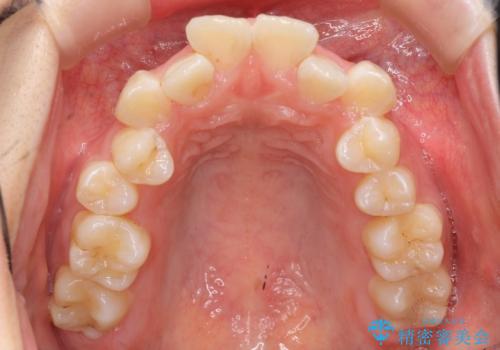

上下の小臼歯を抜歯しています。

矯正用インプラントアンカーを使用してしっかり前歯を下げたため、口元が大きく改善しています。